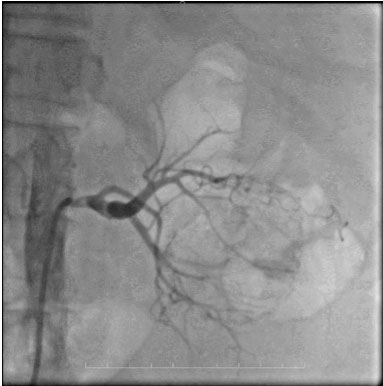

During follow-up, the patient experienced recurrent episodes of hematuria, requiring additional packed red blood cell transfusion. Due to the patient’s cardiac condition, she was deemed unfit for surgery, and conservative management was continued. The patient’s caregivers were counseled regarding the necessity of RAE for hematuria control and the subsequent delayed radical nephrectomy. Under the care of the cardiologist, renal artery angioembolization was performed using endovascular coil placement (Figure 3). The procedure was uneventful, and the patient was transferred to the urological ward after stabilization. Hematuria was immediately controlled following the procedure.

Figure 3: Post-embolization picture after deployment of endovascular coil.

Share Image: